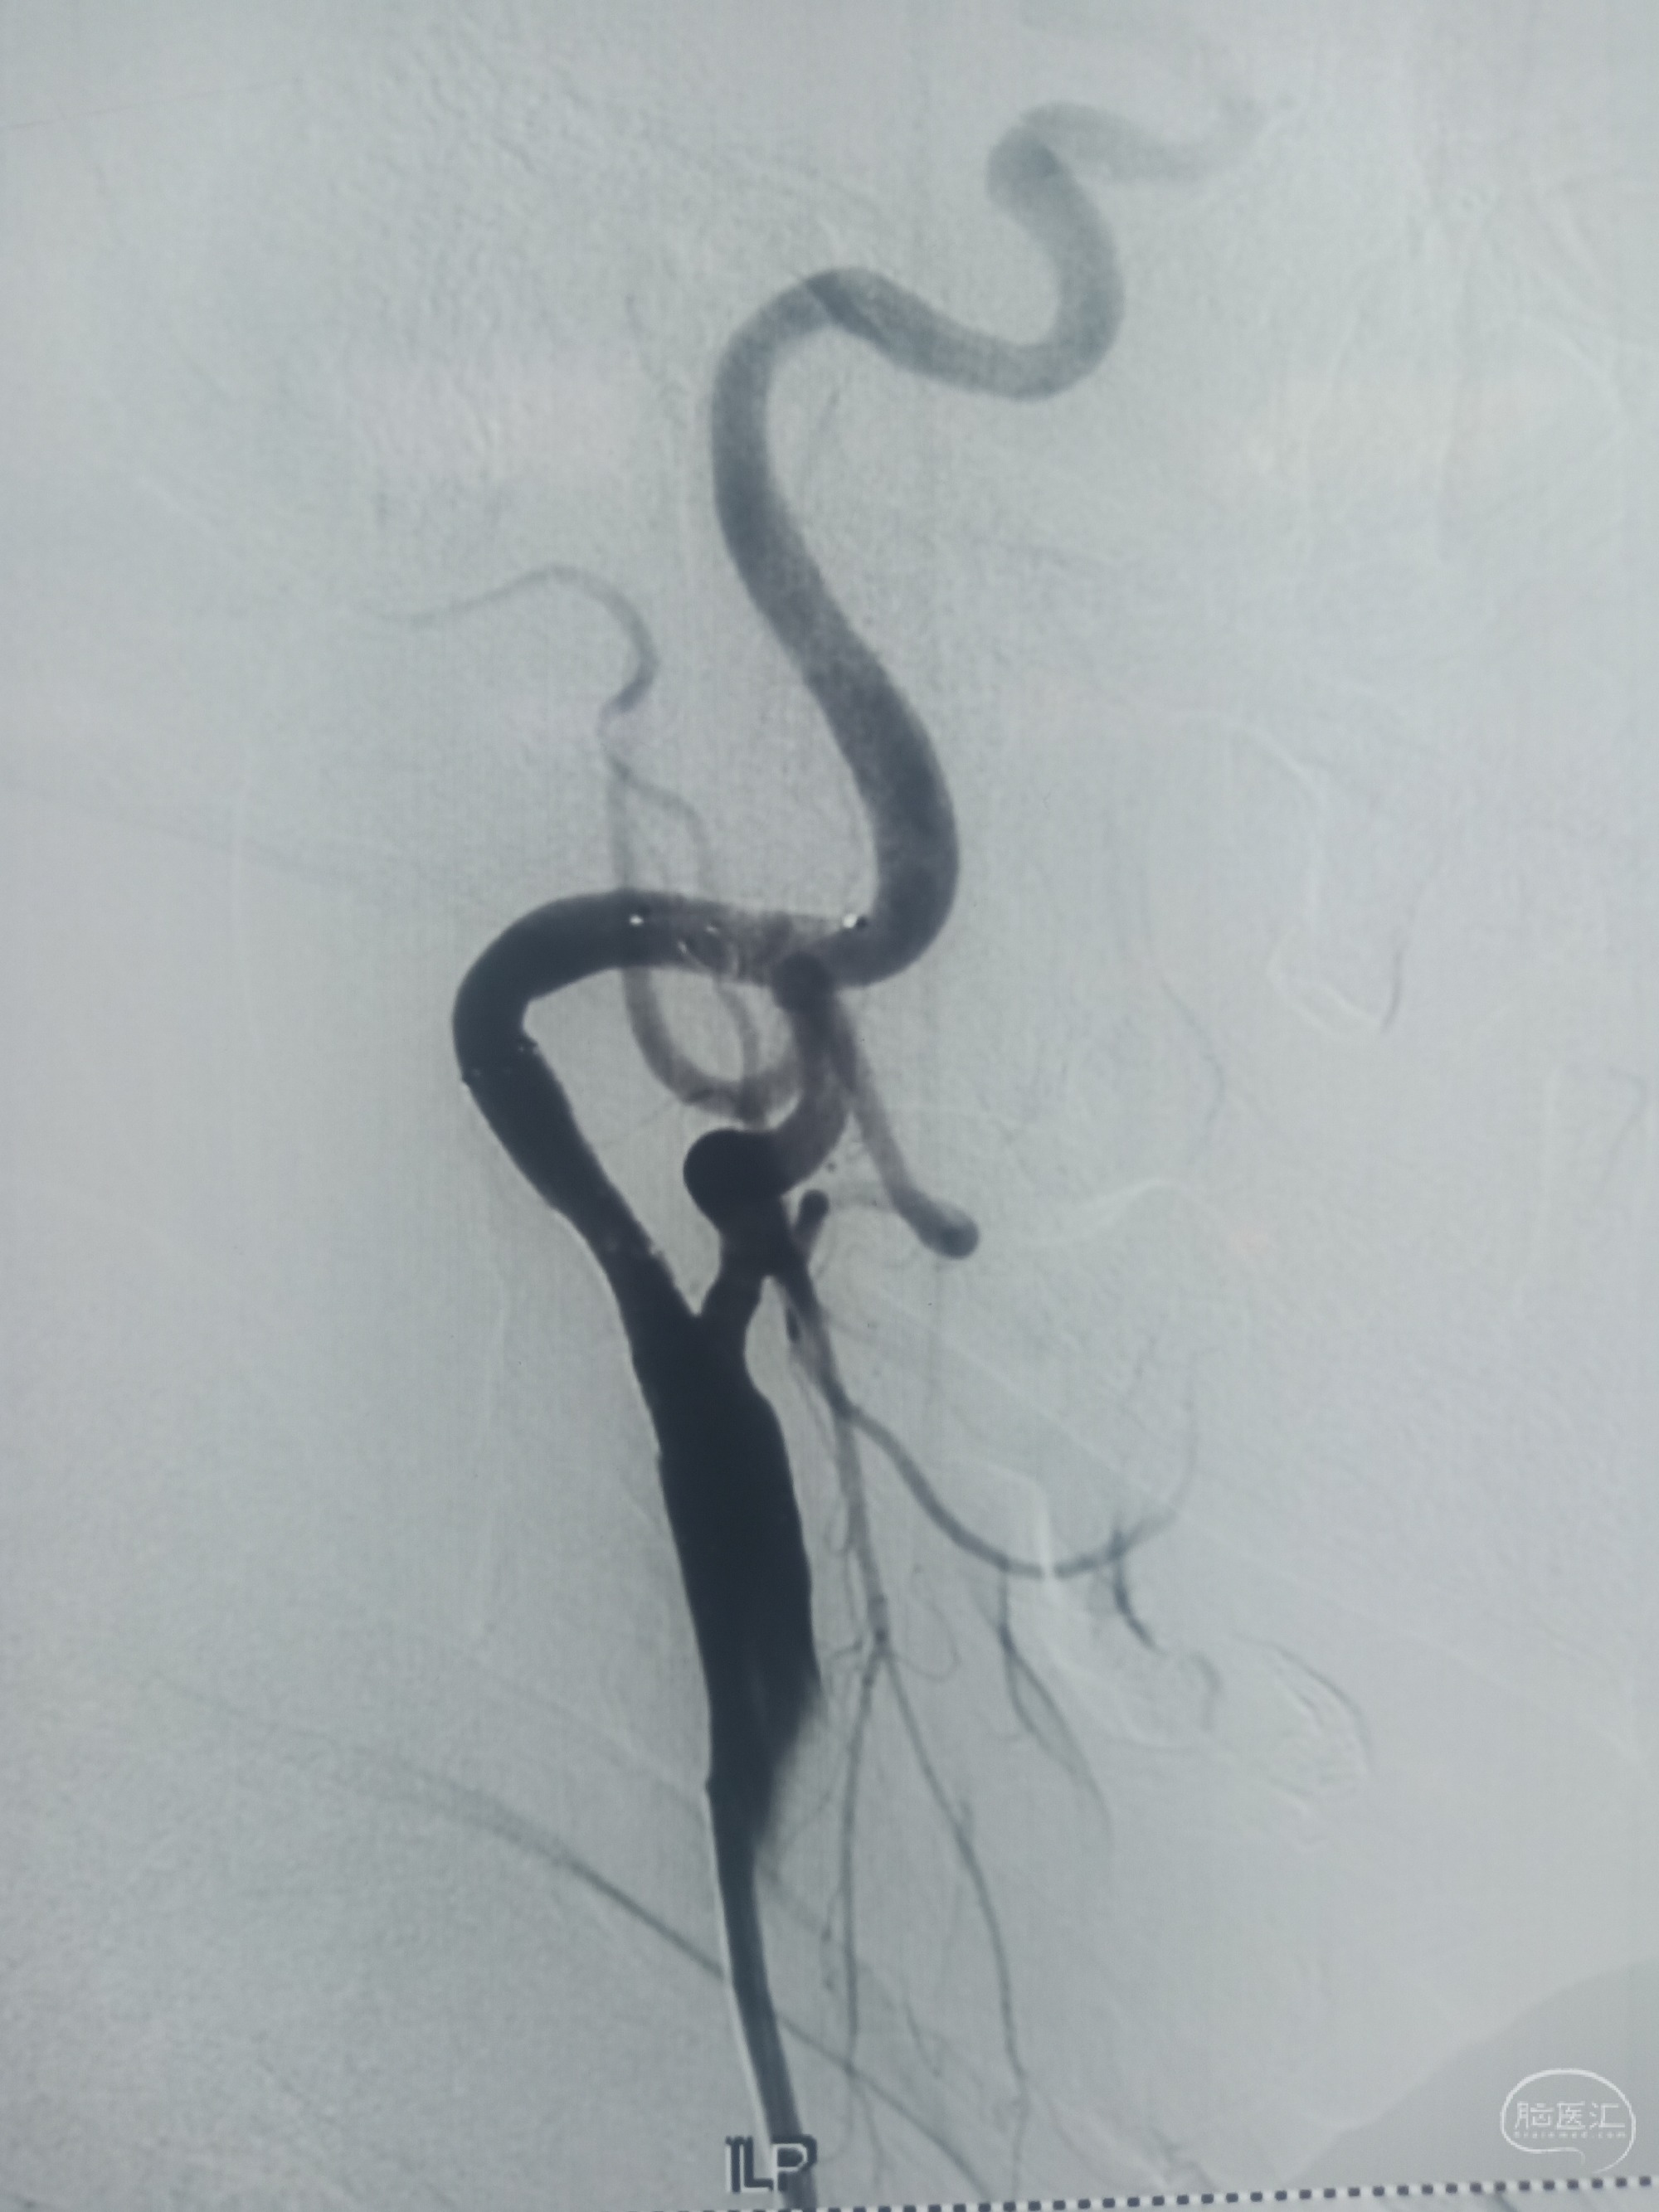

回收保护伞后造影

支架置入后造影,狭窄消失,血流通畅。